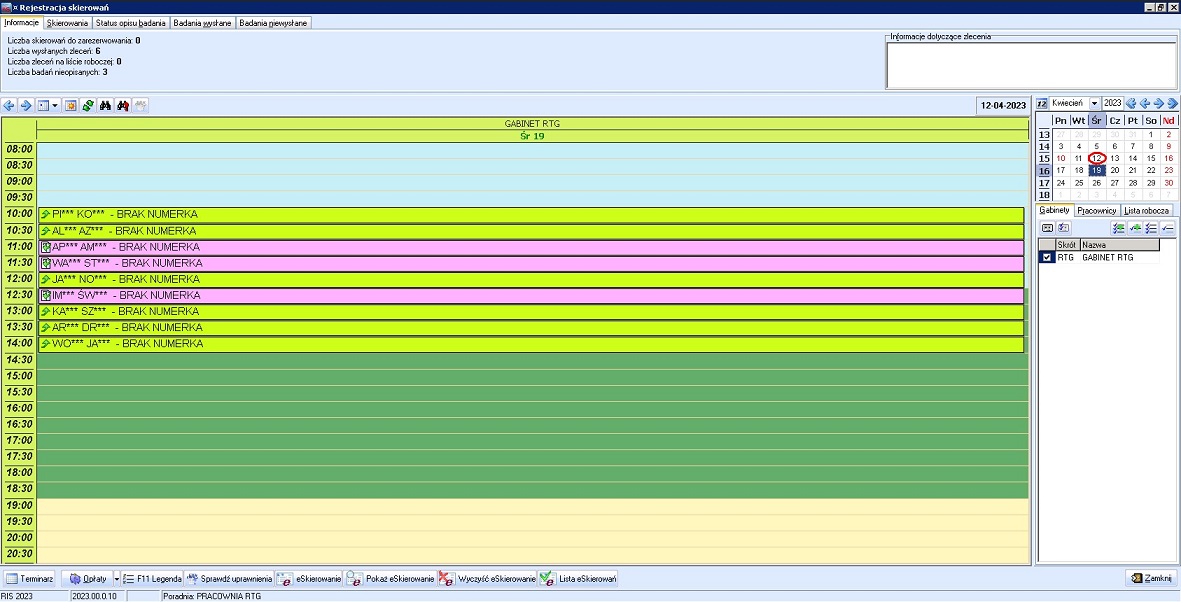

- Oprogramowanie pracowni diagnostyki obrazowej (RIS)

Oferujemy dla naszych Klientów dostawę i uruchomienie rozwiązania informatycznego, które umożliwia obieg informacji medycznej pomiędzy gabinetem lekarskim i pracownią diagnostyki obrazowej. W efekcie nie tylko usprawnia się proces leczenia pacjenta, ale również rozliczenie usług diagnostyki obrazowej. Dodatkowo system umożliwia raportowanie zdarzeń medycznych z diagnostyki obrazowej do systemu P1.

Rozwiązanie zawiera wszystkie elementy informatyczne umożliwiające obieg informacji medycznej, pozwala na tworzenie i udostępnianie elektronicznej dokumentacji medycznej EDM. Integracja pomiędzy systemem medycznym i systemem PACS umożliwia przekazywanie zleceń na badania i odbieranie wyników oraz rozliczenia usług. Opcjonalnie system umożliwia wysyłanie badań do zdalnego opisu.